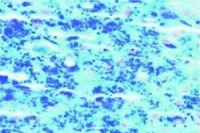

3.肝脏组织检查可观察到肝组织纤维化与肝硬化的程度,并可用化学方法测定肝铁浓度。这是诊断血色病肯定的诊断方法。用普鲁士蓝染色观察可染的含铁血黄素应作为肝活检的常规方法。临床上计算肝铁指数有一定实用价值。

4.骨髓涂片或切片含铁血黄素颗粒增多。尿沉渣中也可见这种颗粒。皮肤活检可见黑色素和含铁血黄素颗粒,约多数患者见到表皮基底细胞及汗腺中有继发于铁沉积的灰色素。